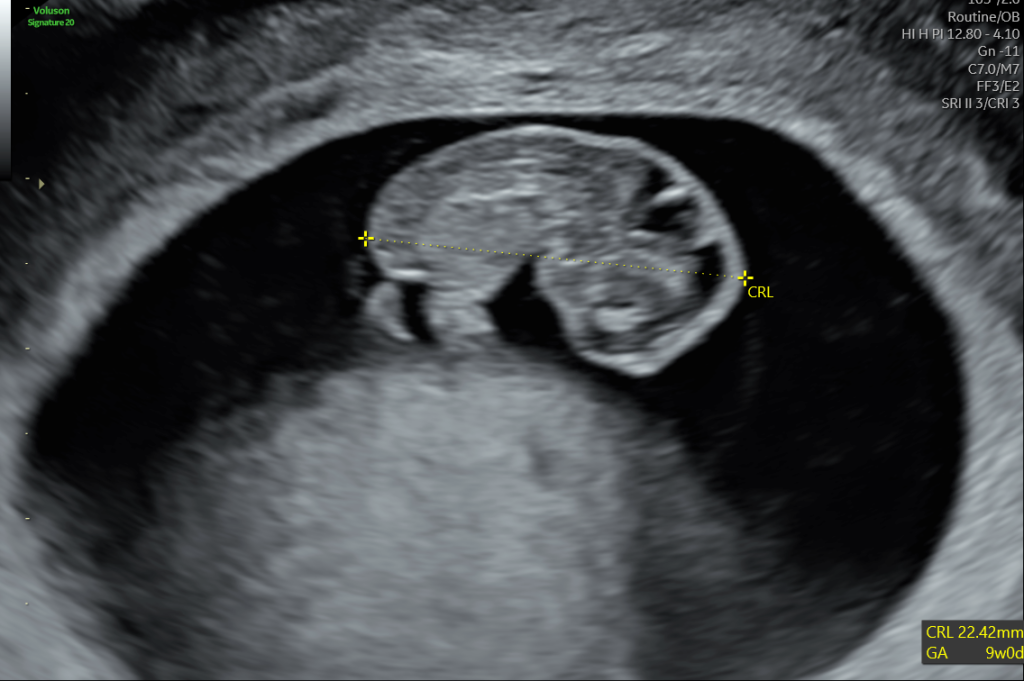

A gestation sac with a yolk sac – no evidence of a baby yet, we can confirm that the pregnancy is in the right place.

A gestation sac with a yolk sac and a foetal pole (baby) with a heart beat. We can measure the foetal pole to date the baby.